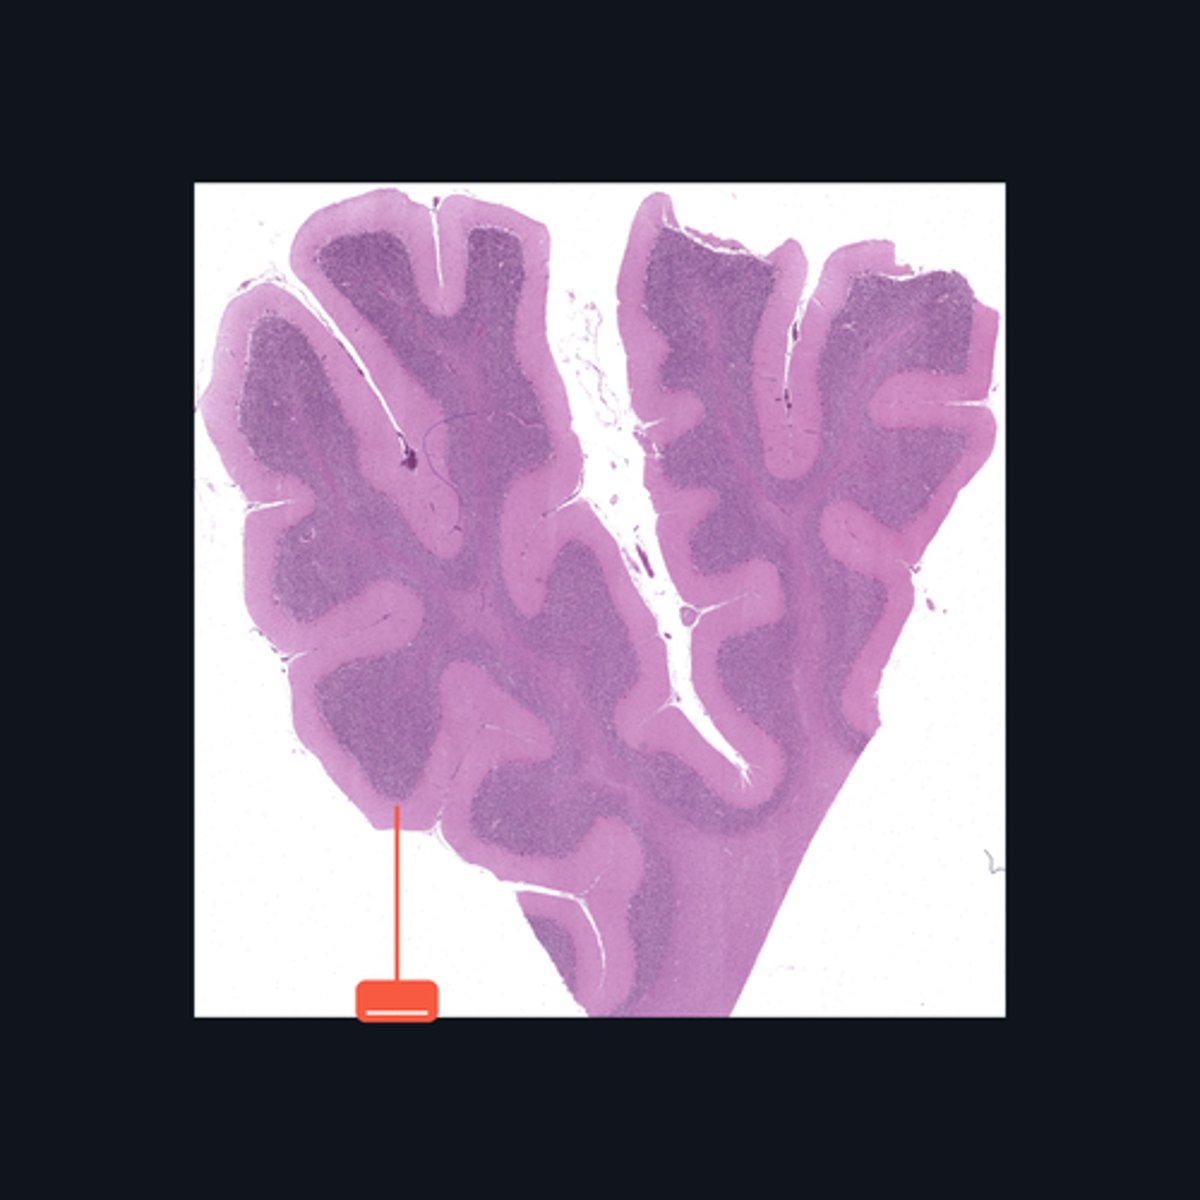

Brain, Cerebral cortex

Identify this structure.

Meninges

What covers this structure of the brain?

Sulci

Outer surface of cerebral hemisphere is highly folded to form convolutions known as

Plexiform (Molecular) Layer, Outer Granular Layer, Pyramidal Cell Layer, Inner Granular Layer, Ganglionic Layer, Multiform Cell Layer

What are the six poorly-designed layers of this structure?

Folia

The surface of the cerebellum exhibits transverse folds called the _____.

Purkinje cells

This middle layer of the cerebellar cortex consists of a single layer of pear-shaped multipolar neurons called _____.

Granule cells

The layer is densely populated by small, round to oval neurons called _____.